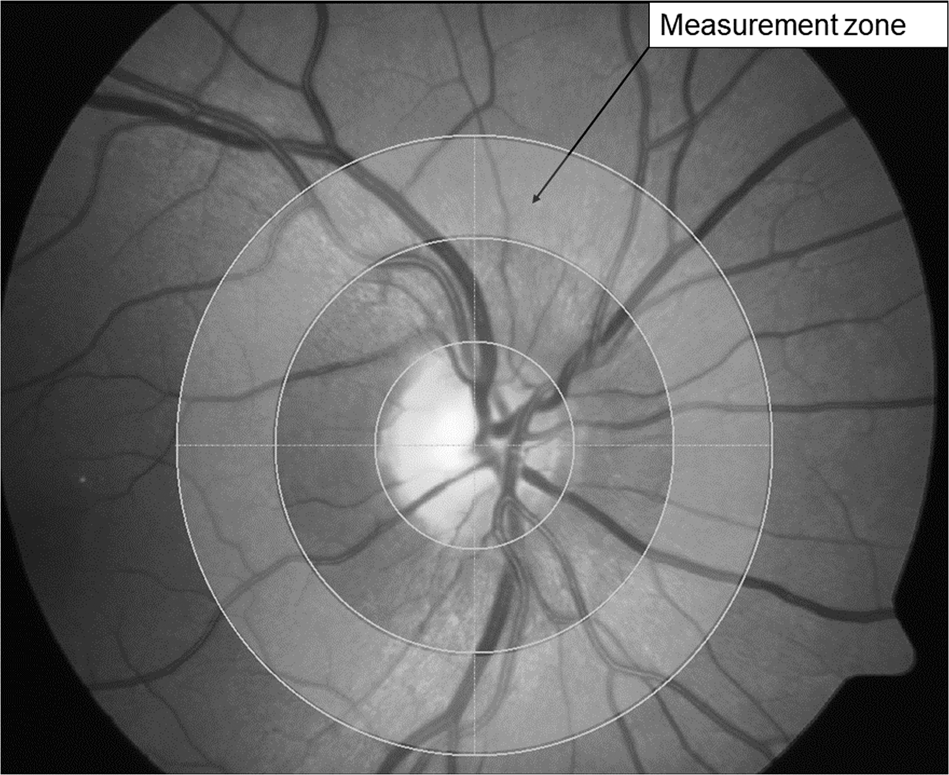

Fig. 2: Measurement annulus.

The shaded area in fundus image represents the concentric measurement annulus around the optic disc which is ½ disc diameter away from the optic nerve head margin and ½ disc diameter in width.